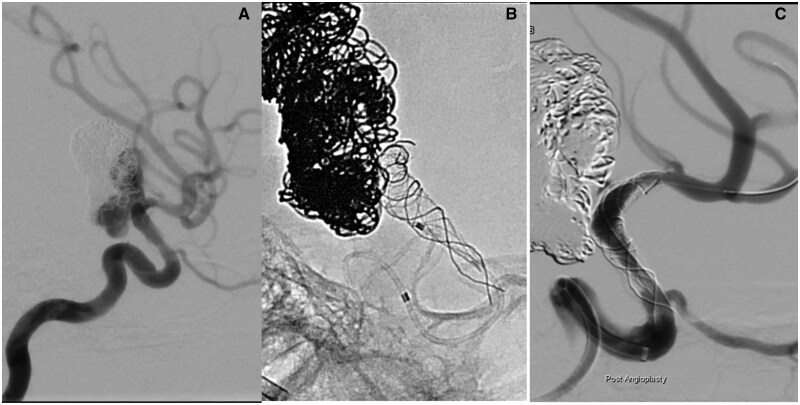

A 28-mm diameter and partially thrombosed intracranial aneurysm was found in a 10-year-old boy on an MRI for non-specific headaches. The large neck incorporated the left internal carotid artery (ICA) termination and proximal middle cerebral artery. Treatment was planned to prevent further growth and rupture. Because of the difficult anatomy, a braided stent was first placed across the aneurysm neck as a scaffold to allow for the placement of a flow-diverting stent after its endothelialisation. However, severe stent-induced endothelial hyperplasia was encountered when the flow diverter was inserted. This resulted in a transient ICA occlusion during the procedure before flow was restored by angioplasty. As a result, the patient suffered a mild transient dysphasia but permanent loss of vision in the left eye. All antiplatelet medications were stopped 1 year after the procedure without problem. The aneurysm has remained fully occluded in the 7 years since.